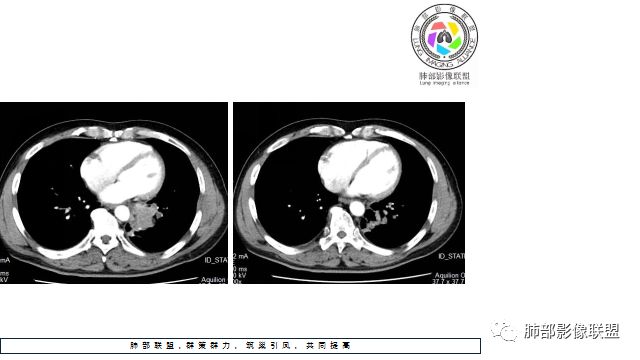

1.左下肺门区巨大肿块,支气管显示不清,轻度阻塞性炎症,没有明显肺不张,提示管腔受压狭窄可能性大于堵塞,这较少见于鳞癌。

4.病灶内有肺动脉走形,血管局部受压,未见破坏,病灶乏血供,呈血管包埋或血管造影征;侵袭性力强及破坏力弱、血管漂浮都符合SCLC,所以鳞癌的可能性也不大。

5.左肺门块影或淋巴结肿大,竭力挤兑肺门血管结构,呈冰冻肺门;有时候SCLC可以单独呈现冰冻肺门,而没有没有冰冻纵隔。

7.须特别注意的是,肺门区的融合块影,不排除它可能仅仅为转移淋巴结。